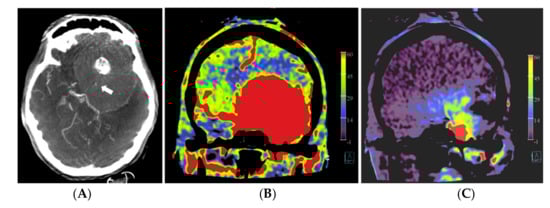

Figure 1.

Example of PBV images pre- and post-embolization with manually drawn regions of interest (ROIs) in a patient with a right frontal convexity atypical meningioma (patient no. 2). Axial post-contrast T1-weighted MRI image (A) shows the tumor with vivid enhancement and intralesional large vessels in a spoke wheel pattern. According to Wen et al. [21], handheld ROIs for PBV value measurements are drawn on PBV images after aortic root contrast injection in axial plane and in sagittal plane before embolization (axial reformation in (C) and sagittal reformation in (D) and after embolization (axial reformation in plane (F), reformation in sagittal plane is not shown) at the level of the largest tumor area. To confirm correct delineation of the PBV measurement area, PBV series were fused with the fill run series (B). Reference PBV measurement on the contralateral side was done using an elliptical ROI in sagittal plane reformation (E).